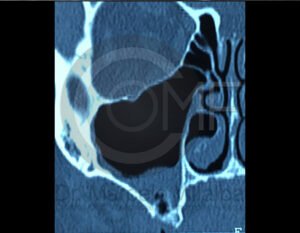

Es una conexión entre la cavidad oral y el seno maxilar que puede ocurrir tras extracciones o infecciones. Su tratamiento busca cerrar adecuadamente la comunicación para evitar molestias e infecciones sinusales.